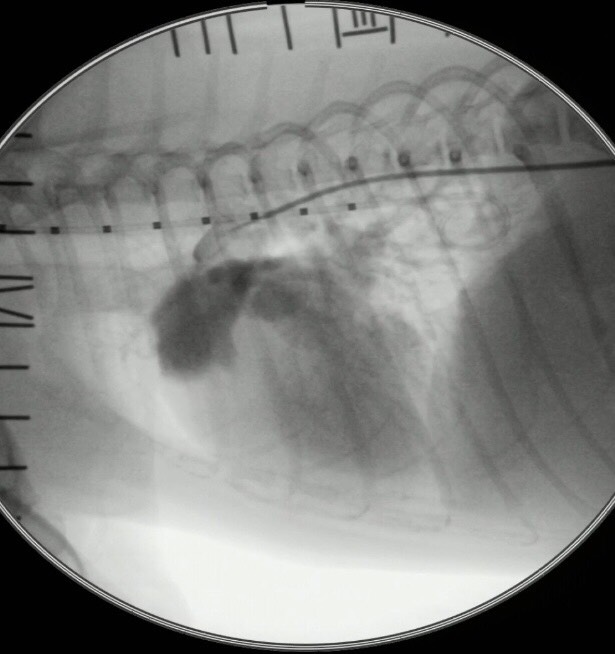

犬に動脈管開存症に対して心臓カテーテル手術を行なった症例

今回は健康診断で、心雑音が聴取され、各種検査で動脈管開存症と診断し心臓カテーテルでの手術を実施した症例を紹介させて頂きます。

今回、治療法としてコイル塞栓術を実施いたしました。

写真は、コイル塞栓の一連の流れを掲載させて頂きました。

症例は術後の短絡血流もなく無事に退院できました。